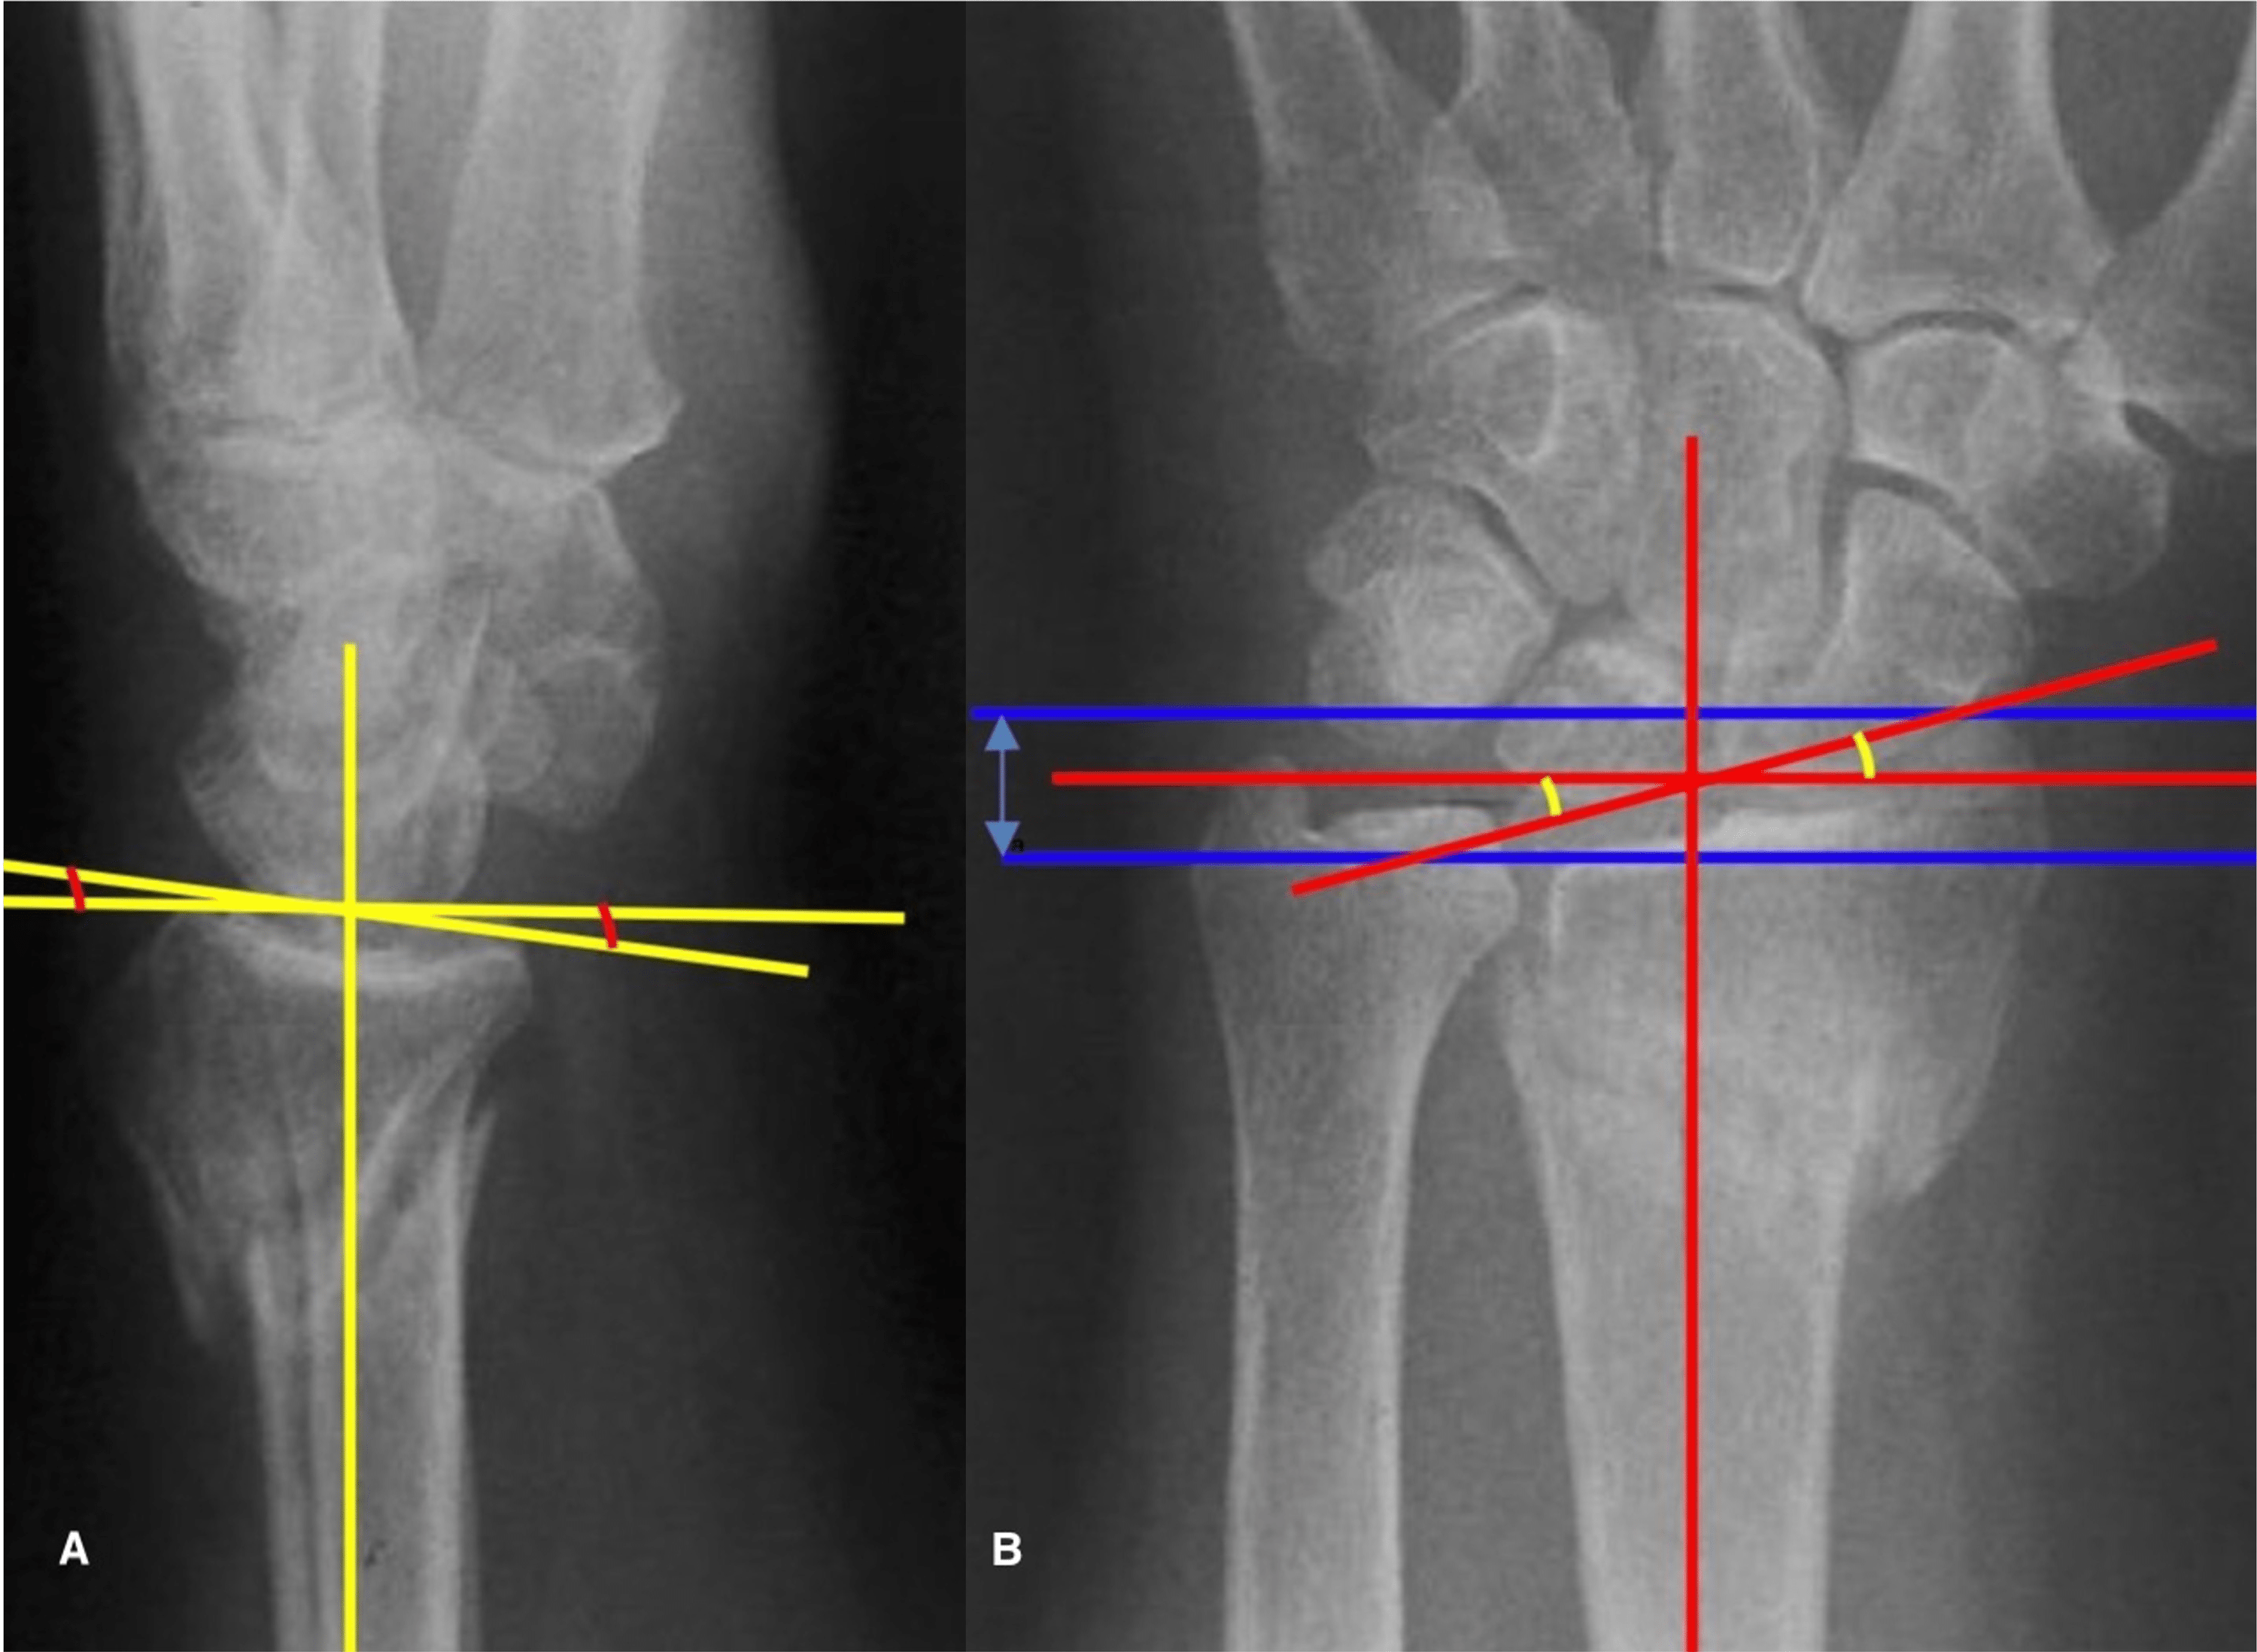

Radiological evaluation of the distal radius. If radial inclination Distal Radius Measurements Distal radius fractures are the most common orthopaedic injury and generally result from fall on an outstretched hand. It is usually caused by a fall onto. Distal radius fractures and does not address distal radius malunion. They occur through the distal metaphysis of the radius, with or without articular surface. In addition to providing pragmatic practice recommendations,. The distal radius. Distal Radius Measurements.

Figure 1 Various tilts and angles at distal radius and ulnar articular Distal Radius Measurements (reproduced with permission from the orthopaedic trauma association). Distal radius fractures and does not address distal radius malunion. Distal radius fractures are the most common orthopaedic injury and generally result from fall on an outstretched hand. It is usually caused by a fall onto. The normal radiographic measurements of the distal radius. The distal radius fracture (drf) is the most. Distal Radius Measurements.